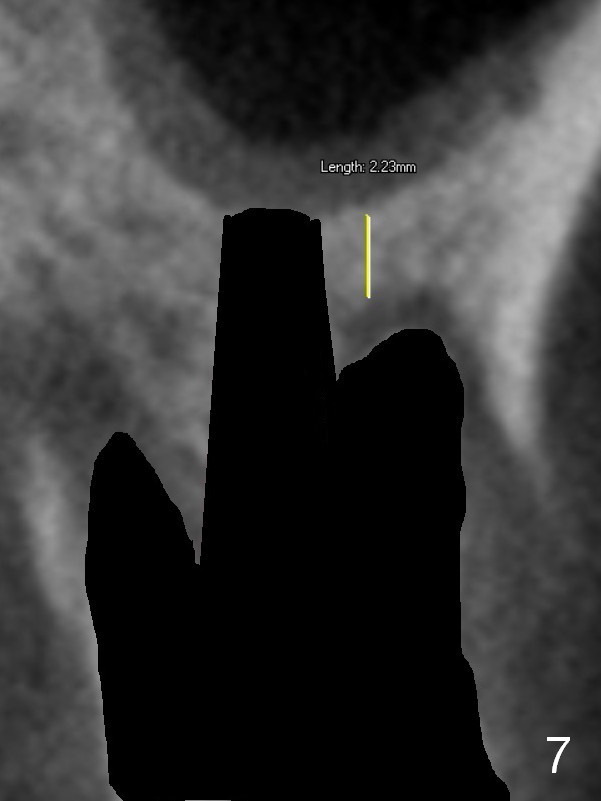

The septal bone is dense and the osteotomy is enlarged by alternating use of drills and expanders. By the time 3.8 mm ME is tapped in (Fig.6), the buccal plate of the septum is perforated. The ME is stable, in spite of the fact that it is only supported by 2-3 mm bone buccally (Fig.7). Continuously alternating use of MEs and drills leads to placement of a 5x11 mm implant with 30 Ncm insertion torque and sinus lift. After placement of bone graft (Fig.8 *) and 5x4(3) mm pair abutment (A), an immediate provisional is fabricated. Red dashed lines in Fig.6,9 represent the mesial outline of the socket, whereas black dashed in Fig.6 sinus floor. It suggests that the implant is stabilized by relatively small amount of native bone. Although IBS implants have aggressive thread patterns, a proper apical osteotomy should be prepared in the depth (perforates the sinus floor in this case) and diameter (4.3 mm drill) prior to placement.